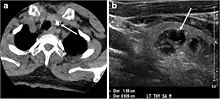

Fig. 7. A 51-year-old female patient post total thyroidectomy for PTC with elevated thyroglobulin measurement. an Axial non-enhanced CT scan of the neck at the level of the thyroid bed demonstrates a well-defined, rounded, homogenously dense soft tissue situated between the trachea and left internal jugular vein (white arrow). b Transverse ultrasound image of the neck demonstrates a well-defined, homogeneous, hypoechoic soft tissue nodule measuring 6 mm (white arrow) with no detected micro-calcifications. Biopsy showed a predominantly residual normal thyroid tissue with micro-foci of PTC.[1]